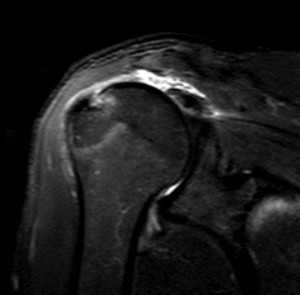

Разрыв вращательной манжеты - также характерное повреждение области плеча - может быть связан как с травмой, так и дегенеративными процессами. Разрывы вращательной манжеты бывают полные и неполные. Кроме того, по МРТ плечевого сустава выделяют 3 градации, в основе которых лежит не только изменение сигнала на Т2-зависимых томограммах, но и морфологические изменения сухожилия.

МРТ. Корональная Т2-зависимая томограмма с подавлением сигнала от жира. Полный разрыв сухожилия надостной мышцы.

При МРТ плечевого сустава косвенным признаком разрыва вращательной манжеты служит высокий сигнал на Т2-взвешенных от поверхности сустава до субакромиальной (субдельтовидной) сумки. Частичные разрывы чаще всего по передней поверхности сухожилия м.supraspinatus, реже примыкая к большой бугристости или сухожилия м. infraspinatus.

МРТ плечевого сустава. Т2-взвешенная корональная МРТ. Субакромиальное скопление жидкости - косвенный признак разрыва вращательной манжеты.